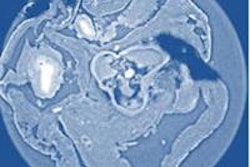

X-ray phase-contrast imaging is a method that uses the refraction of x-rays through a specimen instead of attenuation resulting from absorption. The images produced with this method are often of much higher quality than those based on absorption, according to the authors of the study published on 26 June by Physical Review Letters.

From a single measurement, researchers obtain an attenuation image, the phase image, and a dark-field image, explained lead author Irene Zanette, PhD, the chair of biomedical physics at TUM. The phase image can be used to measure accurately the specimen's projected thickness. The dark-field image can be just as important, because it maps structures in the specimen too small to be resolved, such as cracks or fibers in materials.

As a single-shot technique, Zanette and colleagues noted that speckle imaging is a perfect candidate for an efficient extension to phase-contrast tomography, which would give 3D insight into the microstructure of the intended target.